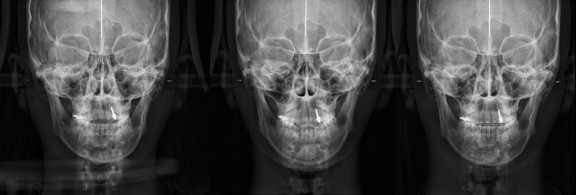

Not long ago, a practicing physician from Prague visited my clinic during orthodontic bracket treatment. She was diagnosed with facial asymmetry and body misalignment, and experienced MCB splint therapy. She was aware that bodily misalignment is related to asymmetry in the facial bones.